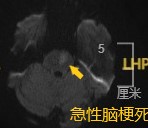

急诊检查头颅磁共振-DWI:左侧脑桥急性脑梗死!